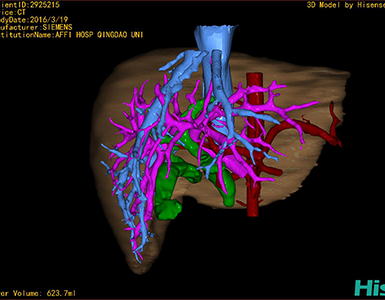

CT结果输入海信CAS系统后行3D重建及手术规划后,于2016-3-22全麻下行“胆总管囊肿切除+胆囊切除+胆总管-空肠吻合术”手术治疗:

术前三维重建及手术方案设计:

将0.625mm双源薄层CT资料的静脉期和动脉期Dicom格式文件导入海信CAS系统。

通过调节窗宽窗位调整CT序号,对肝实质,胆囊,下腔静脉,肿瘤,肝动脉、门静脉及肝静脉等进行三维重建;系统自动计算肝脏体积。

术前手术方案的规划。

术前三维重建:

重建图片